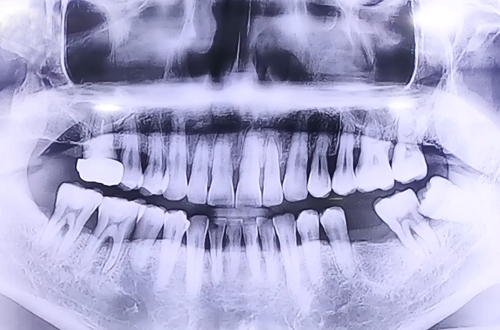

AFTER

맨 앞쪽에 발치 후 오랜 기간이 지난 큰 어금니 부위에는 자연 식립 임플란트를 진행해 드렸고

사랑니와 그로 인해 흔들림이 심했던 큰 어금니를 둘 다 발치한 뒤에 원래 있어야 하는 자리에

뼈이식과 임플란트를 동시에 진행하며 반듯하게 심어 뚜껑을 덮어 마무리해 드렸습니다.